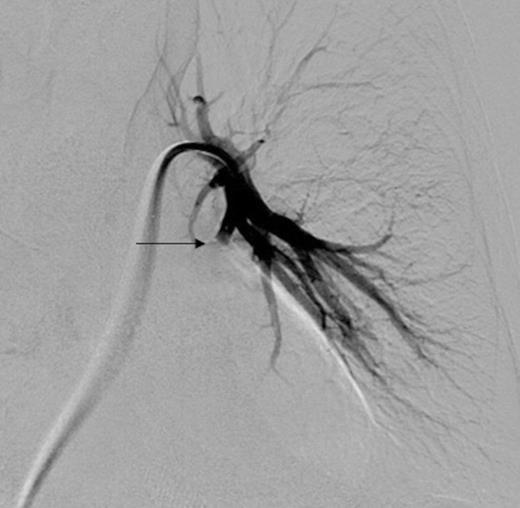

Coronal CT image in arterial phase demonstrating a 28mm diameter left lower lobe pulmonary artery aneurysm in association with a fluid collection

Three days later he presented with significant haemoptysis. A CT pulmonary angiogram (CTPA) demonstrated an increase in size of the PAA from 14mm to 28mm (Figure 1) diameter. A radiology opinion was sought and the patient transferred to the angio-suite for intervention.